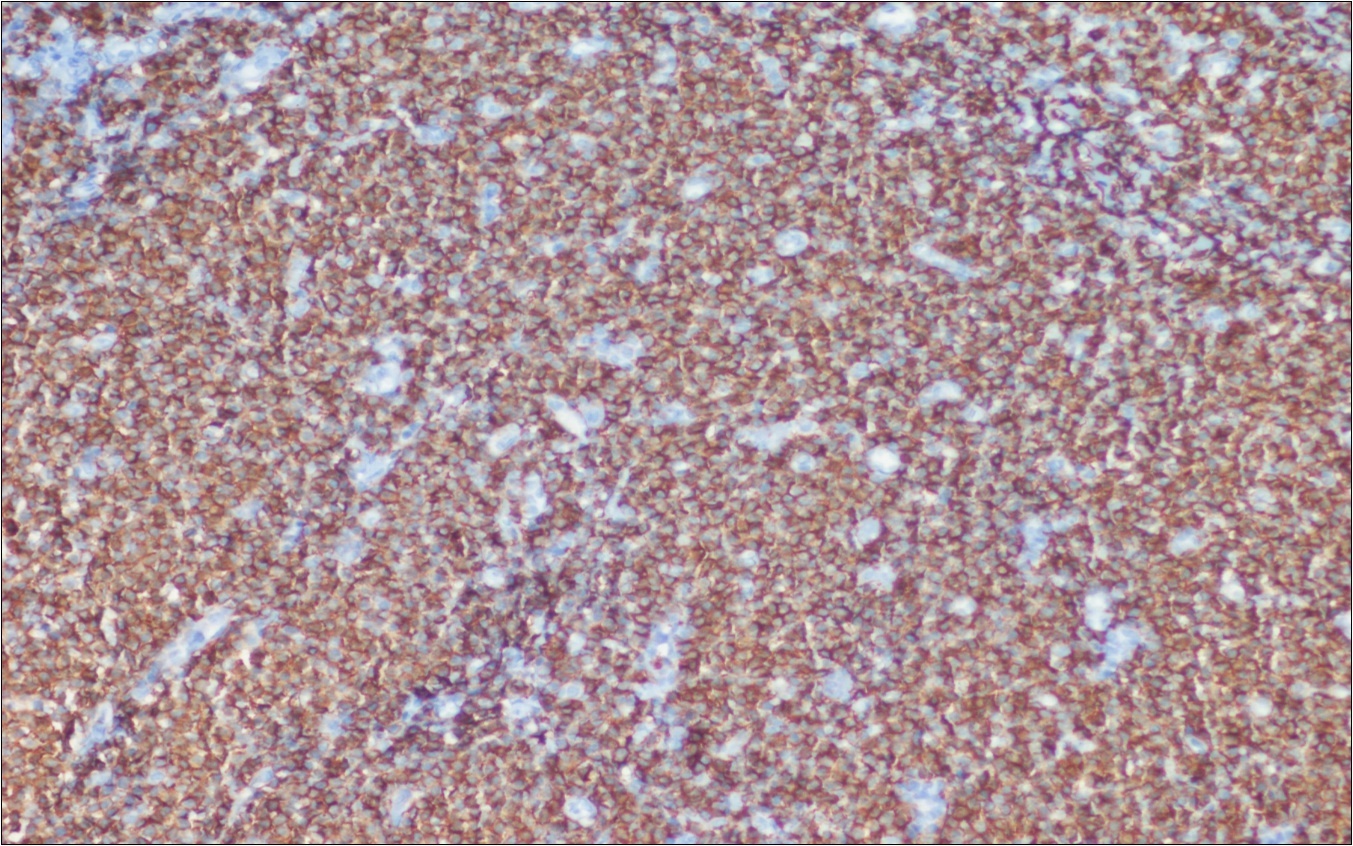

A 63-year-old woman presented to the Department of General Surgery as an outpatient with abdominal pain. Physical examination showed the signs of acute appendicitis and appendectomy was performed. During microscopic examination, a small focus of atypical monotonous lymphoid cell population was seen and the material was sampled totally. The pathological examination revealed MALT lymphoma (Figure 1), with diffuse positivity of cluster of differentiation (CD) 20 (Figure 2), CD 79a and B-cell lymphoma (Bcl- 2) (Figure 3) with just a few CD3 positive lymphoid cells. However, no evidence of adenocarcinoma was found in the appendectomy specimen. After the diagnosis of lymphoma, a complete colonoscopy was planned and this revealed a solid tumoral mass in the caecum measuring 5x4x4 cm. Computed tomography of the abdomen and pelvis revealed mesenteric lymphadenopathy associated with a mass in the caecum with multiple nodules in liver consistent with metastasis (Figure 4). Frozen sections were not obtained since the treatment method would not be affected. The patient underwent anterior resection with regional lymphadenectomy, with the pathological assessment of the resected specimen revealing a collision tumor consisting of a poorly differentiated adenocarcinoma extending through the muscularis propria with MALT lymphoma (Figure 5). Microscopic evaluation of the 11 regional lymph nodes in the mesentery of the resected colon and liver biopsy showed diffuse infiltration of MALT lymphoma with metastasis of adenocarcinoma (Figure 6). According to immunohistochemistry, atypical lymphocytes were positive for CD 20, Bcl-2, and negative for CD3, CD5, CD10, CD23, Bcl-6, terminal deoxynucleotidyl transferase, and cyclin D1. The proliferation fraction (MIB-1 immunostaining) was approximately 20%. The morphological and immunohistochemical findings were used to confirm the diagnosis of synchronous presentation of MALT lymphoma and colon adenocarcinoma within the caecum, mesenteric lymph nodes and liver metastases.

Figure 2.CD 20 positivity of lymphoid cells (CD20, x200)

Figure 3.Bcl-2 positivity of lymphoid cells (Bcl-2, x200)